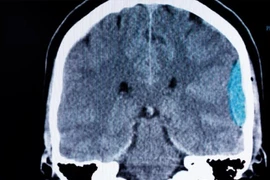

Trong quá trình mổ, phát hiện một dây chằng dính từ vòi trứng phải, vắt qua 1 đoạn ruột non gây nghẹt ruột non hồi tràng, đoạn ruột phía trên giãn to, tím đen (chưa có dấu hiệu hoại tử ruột).

tac-ruot-sau-mo-1.jpg

Dây chằng vắt ngang hồi tràng, đoạn ruột phía trên giãn to, tím - Ảnh BVCC